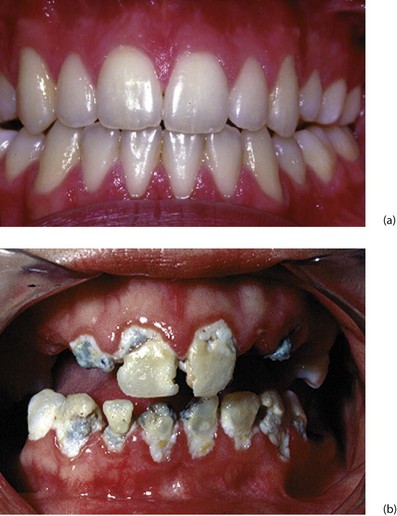

Fig. 48.5 Gingivitis and periodontitis

(a) Normal healthy gingivae. (b) Chronic gingivitis showing accumulated plaque and calculus around the gingival margins. At this stage, no alveolar bone has been destroyed and the inflammatory process is potentially reversible. Many of these teeth had to be extracted, however, because of rampant caries